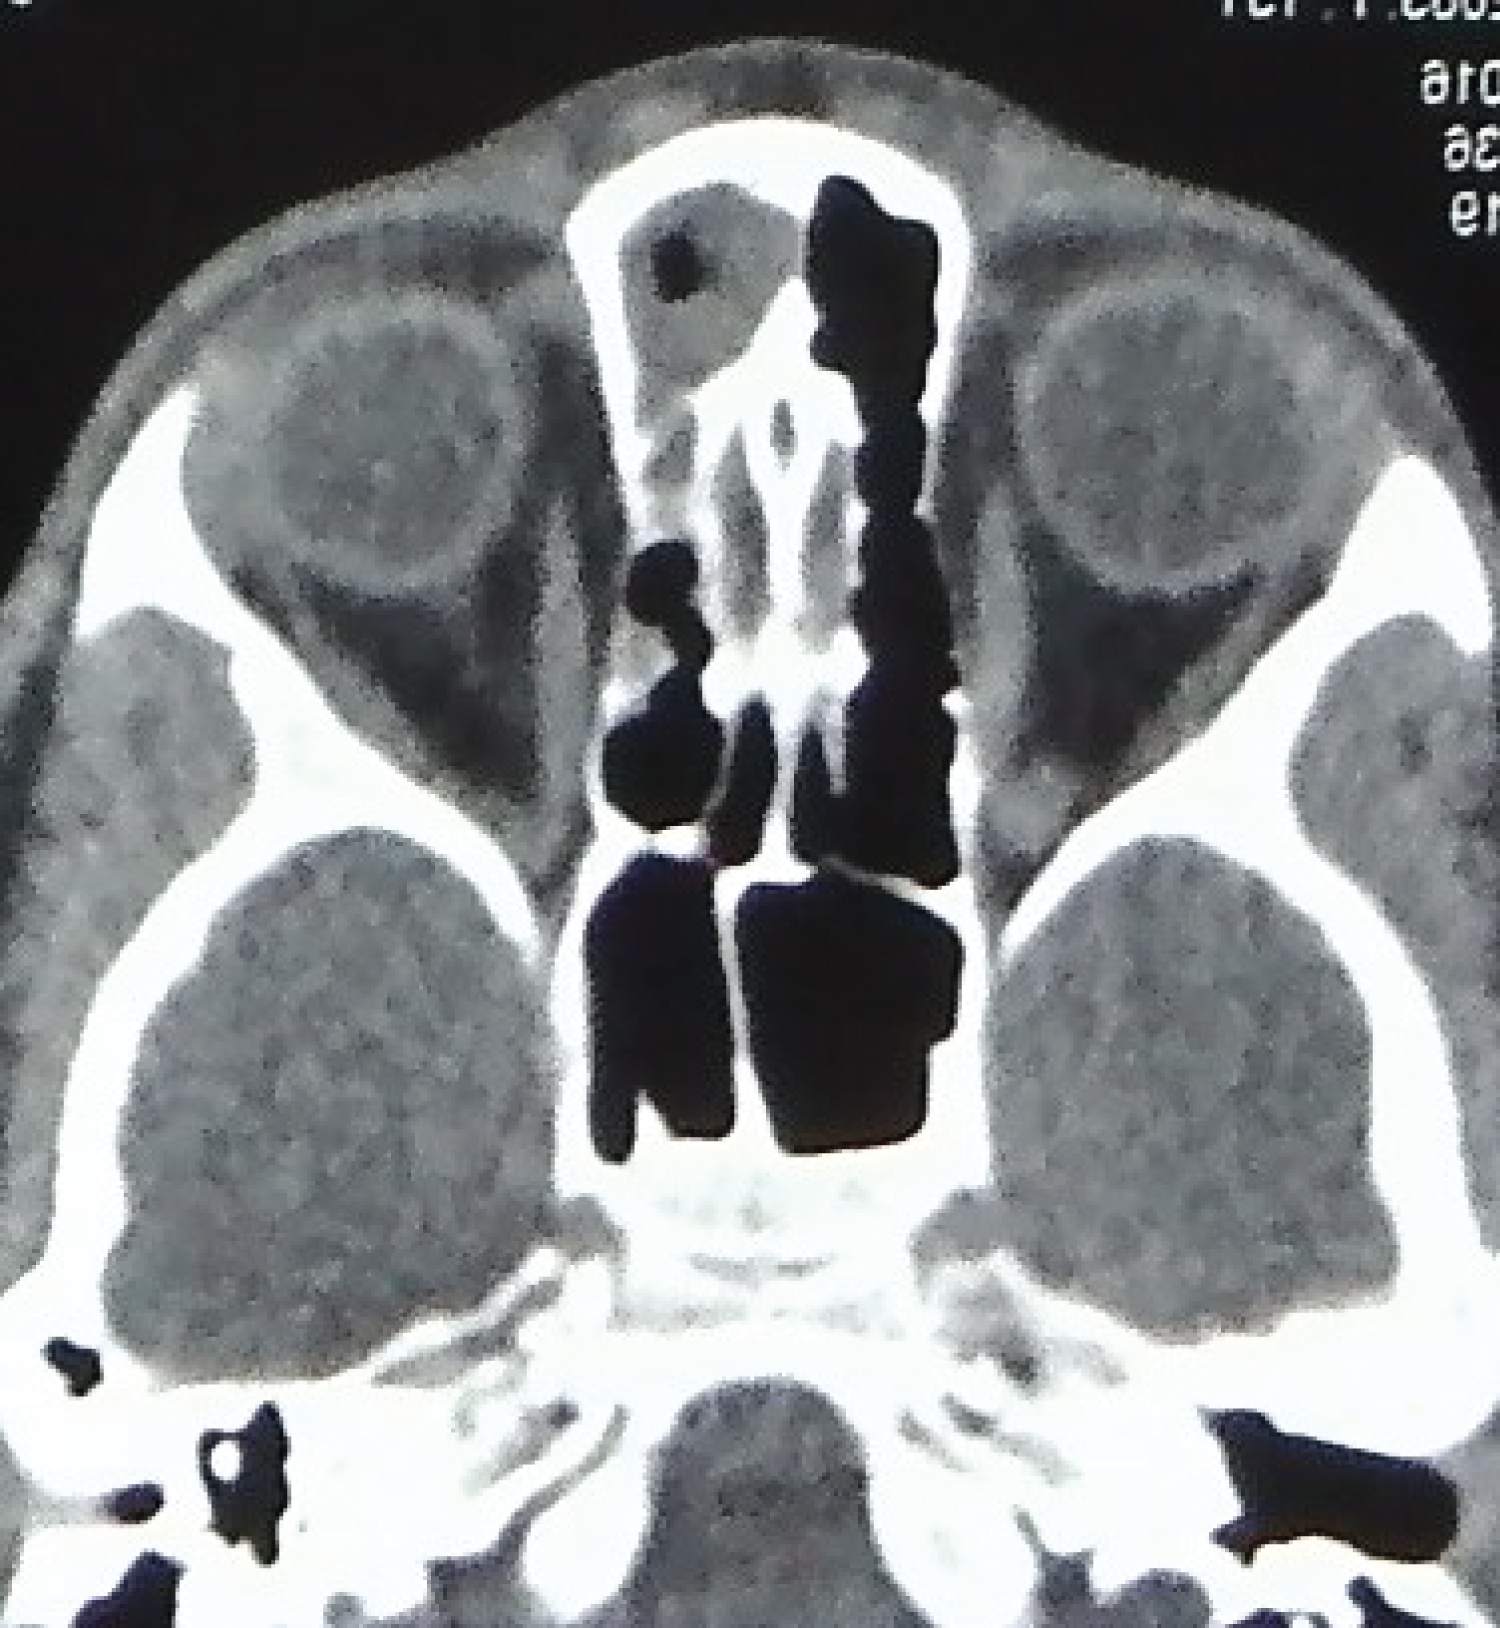

The swelling was non tender, smooth, diffuse, globular, not adherent to skin, the deeper margins were insinuated between the nasal bones. There were no signs of inflammation. A midline punctum was noted. A provisional diagnosis of NDSC was made. Contrast enhanced computed tomography (CECT) of head and neck was done. CECT scan detected a small volume of fluid along the nasal dorsum (Figure 3). There was no evidence of bony erosion along anterior cranial fossa and crista galli appeared to be normal for the age (Figure 4).

Figure 3: Axial cut of CT scan, showing fluid collection on dorsum of nose. View Figure 3

Figure 4: Axial cut of CT scan, showing normal crista galli. View Figure 4

The possibility of a transcranial extension necessitates a thorough radiographic evaluation by CT and magnetic resonance imaging (MRI) [1]. It was believed that CT findings of wide foramen cecum and bifid crista galli, are suggestive of intracranial extension [4]. A number of false positive findings led Penslar to review the radiographic images and conclude that an enlarged foramen caecum and a bifid crista galli did not always correlate with intracranial extension [4]. However, a normal foramen caecum and crista galli certainly rules out intracranial disease [3].